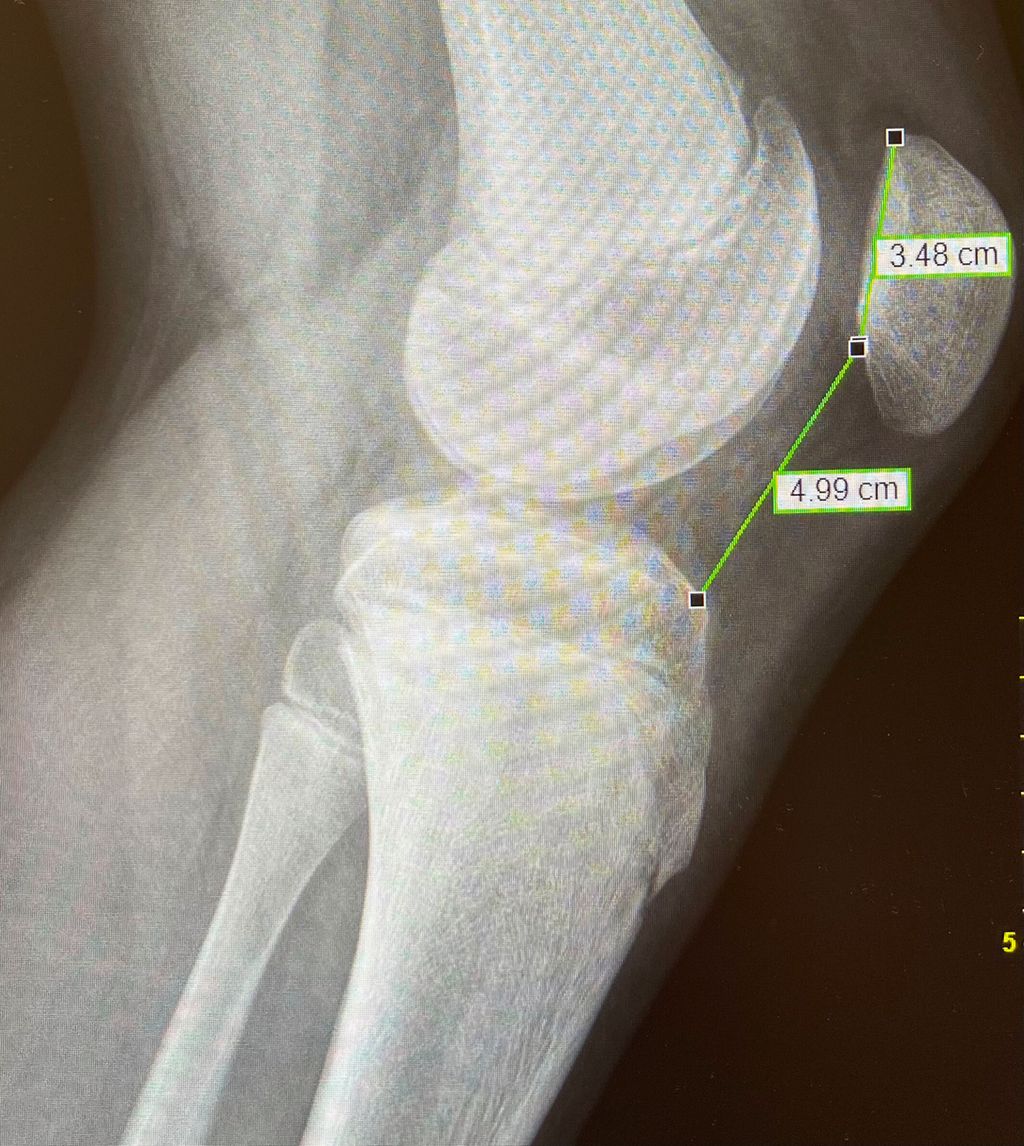

Eine Instabilität bis circa 30° ohne weitere Auffälligkeiten in der radiologischen Untersuchung wird mittels alleiniger MPFL-Rekonstruktion stabil. Ab circa 0–60° Instabilität gibt es zumeist Probleme mit der knöchernen Führung. Dies kann aufgrund eines zu späten Eingleitens der Patella – einer Patella alta – und/oder des Fehlens einer knöchernen Führung (Trochleadysplasie) auftreten. Unserer Meinung nach bedarf es einer Korrektur der Patella alta ab einem Caton-Deschamp-Index >1,2 (Abb.1) und/oder einer LTI (laterale Trochleainklination) von <17° (Abb. 2). Ab 60° ist zusätzlich ein Problem im Bereich des Alignments wahrscheinlich. Bei einer vermehrten Innenrotation des Femurs und der Tibia bei ca. 35° und/oder valgischer Beinachse ab ca. 5° wird eine Korrektur in Erwägung gezogen (Abb.3). Prinzipiell sind wir bei einer Alignmentkorrektur eher zurückhaltend (von manchen Autoren wird bereits eine Korrektur ab 20° Innenrotation empfohlen).5 Ein vermehrter TTPCL-Abstand (lateraler Kraftvektor der Patella) ab circa 24mm kann die Luxation ebenfalls begünstigen und bei einer Patella alta mitkorrigiert werden. Sollte eine knöcherne Stabilisierung notwendig sein, ist bei der Trochleaplastik eine arthroskopische oder offene Technik möglich.

Bei der Patella alta wird der Ansatz knöchern etwas nach distal versetzt. Die Schnittführung ist lateral parallel zur Tuberositas, die Osteotomie erfolgt tangential unter Schonung der Patellasehne. Als Führung können 2 Kirschnerdrähte parallel entlang der Schnittführung eingebracht werden. Vor der Operation wird als Anhaltspunkt die gewünschte Distalisierung errechnet. Es empfiehlt sich jedoch, intraoperativ den Patellastand mittels Bildwandler zu kontrollieren (Ziel ist ein Caton-Deschamp-Index unter 1). Die endgültige Fixierung erfolgt mit zwei 3,5-mm-Schrauben (Abb. 9).8